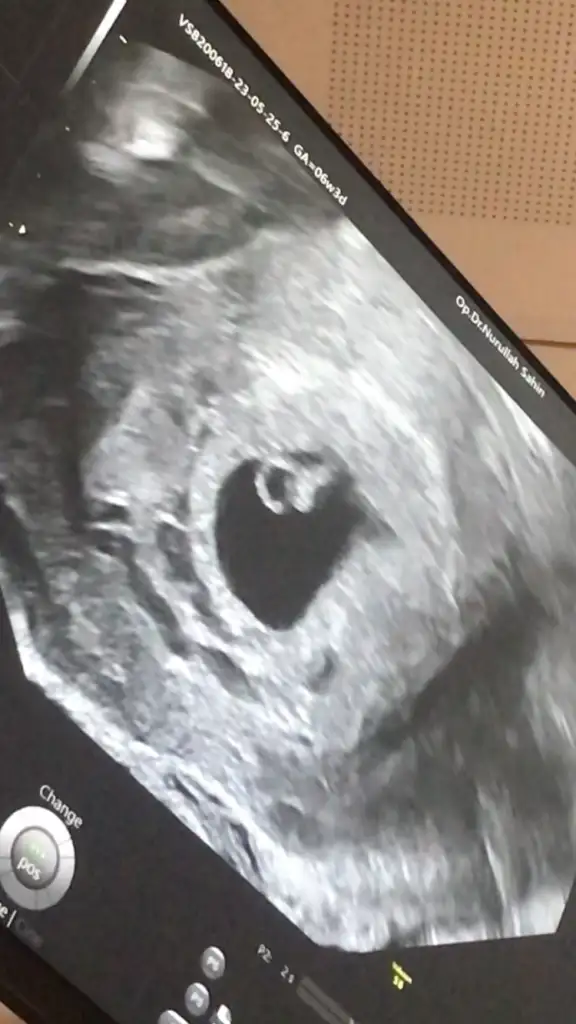

Kızlar bebeğimin kalp atışını duydummm çok şükürrr 6+5 ız ama 6+3 görünüyo dedi. Büyümüş balım yaa mide bulantısı falan yok dedım bazısında olmaz dedı stres yapma dedı. Şükürler olsun 3 hafta sonra tekrar cagırdııı

Hadı yaa doktorumdan cok memnunum valla normalde ıskenderundaydık ama depremden oturu annemlerın yanındaım buradada nurullah beyı onerdıler onunla ılerlıyoruz bakalım